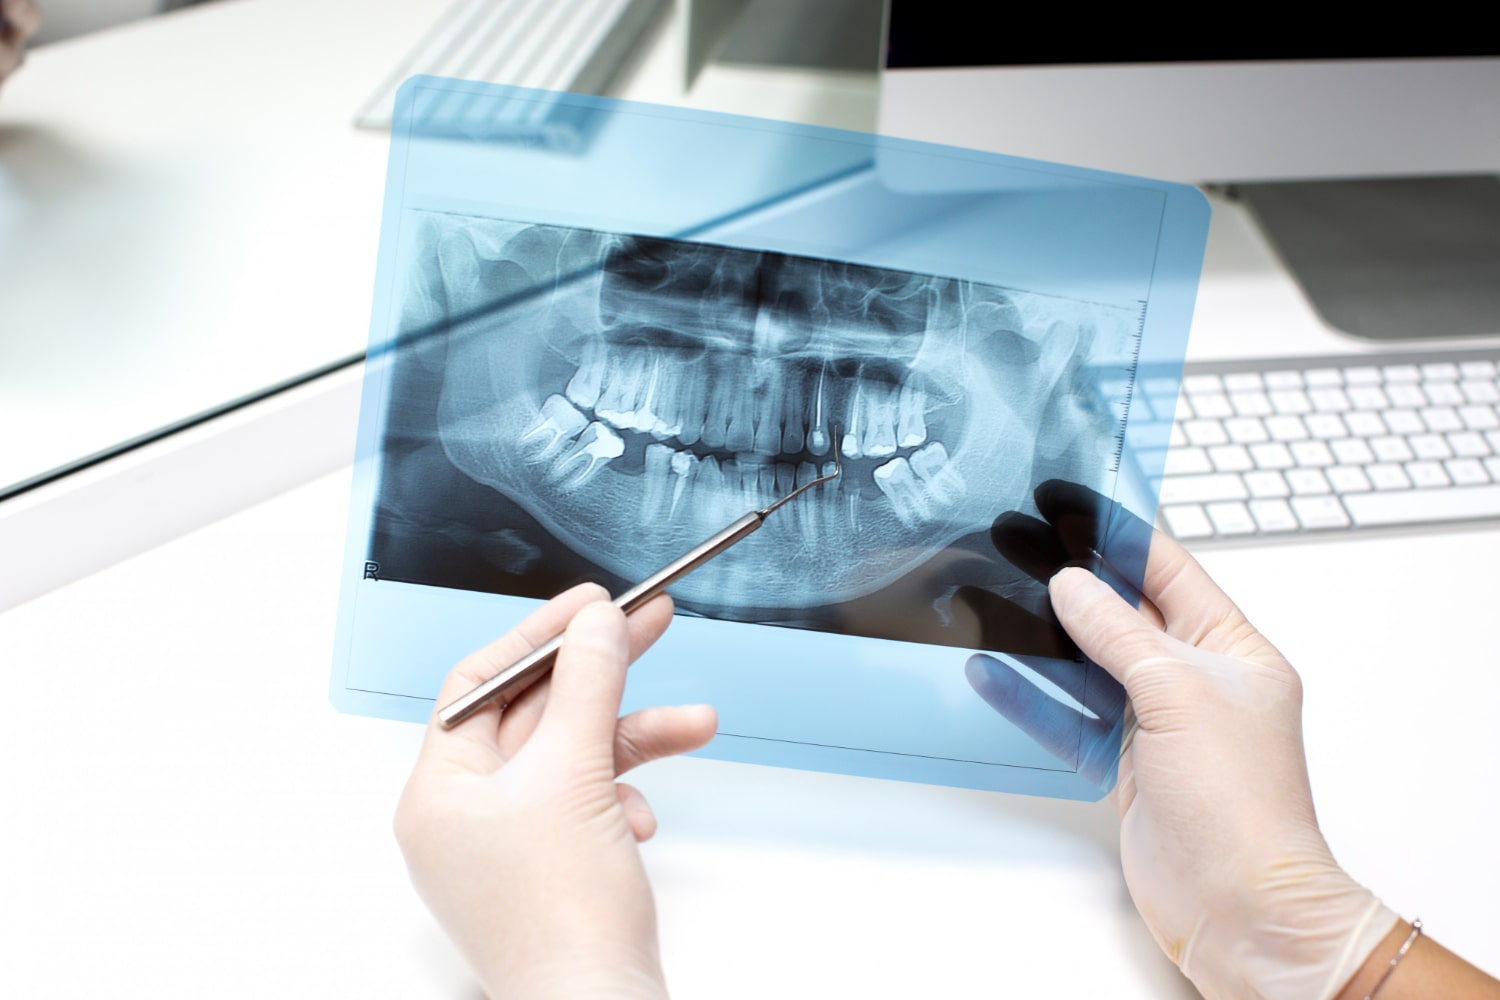

RTG Panoramiczne

RTG panoramiczne to jedno z podstawowych badań diagnostycznych w stomatologii, pozwalające na uzyskanie pełnego obrazu uzębienia, kości szczęki i żuchwy, a także stawów skroniowo-żuchwowych. To szybka i bezbolesna metoda, która umożliwia wykrycie zmian niewidocznych podczas standardowego badania stomatologicznego. Dzięki zdjęciu panoramicznemu lekarz może ocenić m.in. stan korzeni zębów, obecność zębów zatrzymanych czy ogniska zapalne w kościach.

Badanie RTG panoramiczne ma istotne znaczenie nie tylko w planowaniu leczenia zachowawczego, protetycznego czy ortodontycznego, ale także w diagnostyce chorób przyzębia i przygotowaniu do zabiegów chirurgicznych. Wysoka precyzja obrazu pozwala wykryć nawet drobne nieprawidłowości, co zwiększa skuteczność i bezpieczeństwo leczenia.

Co więcej, badanie panoramiczne powinno być wykonywane przy użyciu sprzętu, emitującego możliwie niską dawkę promieniowania. Dzięki temu procedura jest bezpieczna dla pacjenta, a jednocześnie dostarcza szczegółowych informacji niezbędnych w procesie leczenia.